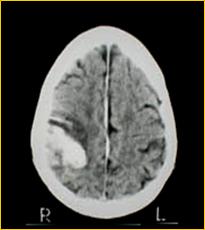

Le patologie che possono portare alla morte cerebrale sono l'emorragia cerebrale da rottura di un vaso intracranico, i traumi cranici ( incidenti stradali, ferite da proiettile ), le neoplasie cerebrali primitive.

EMATOMA SUBDURALE FERITA DA PROIETTILE

L'accertamento della morte cerebrale è competenza di un'equipè medica formata da un neurologo, un rianimatore ed un medico legale e dopo tale accertamento deve trascorrere un periodo di osservazione di sei ore prima che possa essere effettuato il prelievo degli organi.

REPERTO ANATOMICO DI MASSIVA EMORRAGIA CEREBRALE